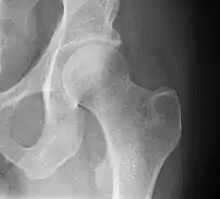

Typically, radiographs are taken of the hip from the front (AP view), and side (lateral view). Frog leg views are to be avoided, as they may cause severe pain and further displace the fracture.[5] In situations where a hip fracture is suspected but not obvious on x-ray, an MRI is the next test of choice. If an MRI is not available or the patient can not be placed into the scanner a CT may be used as a substitute. MRI sensitivity for radiographically occult fracture is greater than CT. Bone scan is another useful alternative however substantial drawbacks include decreased sensitivity, early false negative results and decreased conspicuity of findings due to age-related metabolic changes in the elderly.[16]

A case demonstrating a possible order of imaging in initially subtle findings:

X-ray showing a suspected compressive subcapital fracture as a radiodense line

CT scan shows the same, atypical for a fracture since the cortex is coherent

T1-weighted, turbo spin echo, MRI confirms a fracture, as the surrounding bone marrow has low signal from edema.